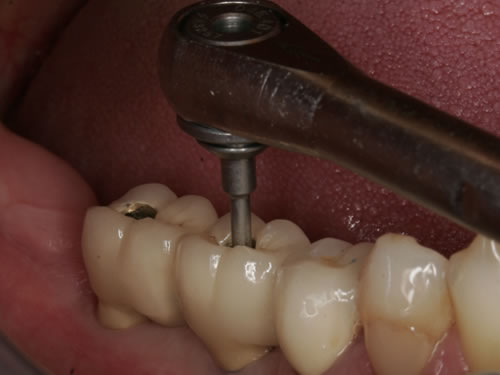

Abb. 3.21: Eingliederung einer verschraubten Brücke mit einem Drehmomentschlüssel.

Bei der verkürzten Zahnreihe oder bei größeren Zahnlücken kann eine Versorgung durch so genannte Verbundbrücken erfolgen (Abb. 8.22, 8.23). Dabei werden die künstlichen Pfeiler mit natürlichen Zähnen verbunden. Eine andere Lösung besteht in rein implantatgetragenen Konstruktionen, denen der Zahnarzt den Vorzug geben wird, wenn die noch vorhandenen Zähne gesund sind und deshalb geschont werden sollten (Abb. 8.24. 8.25).

In den meisten Fällen werden die Kronen oder Brückenteile in den Implantaten zementiert oder verschraubt. Der verschraubte Zahnersatz hat den Vorteil, dass er nach dem Herausdrehen der Schrauben abgenommen werden kann. So lassen sich die Implantate gut  kontrollieren und anfallende Reparaturen können leicht durchgeführt werden. Verschraubungen können auf der Kaufläche oder an die Innenseite gelegt werden. Schön ist eine nicht sichtbare Verschraubung. So werden die Schraubenkanäle auf der Kaufläche meistens mit zahnfarbendem Kunststoff geschlossen. In älteren Systemen sind Stoßdämpfer eingebaut, die die Aufgabe haben, den Kaudruck zu dämpfen. Diese Verschleißteile müssen regelmäßig ausgetauscht werden. Bei verschraubten Versorgungen kann dieses Auswechseln einfacher geschehen als bei zementierten.

Für Einzelzahnlücken werden entsprechende Einzelkronen hergestellt. Sie werden, wie bei natürlichen Zähnen auch, mit Zement auf den Implantaten befestigt oder vom Munde her verschraubt (Abb. 8.26, 8.27).